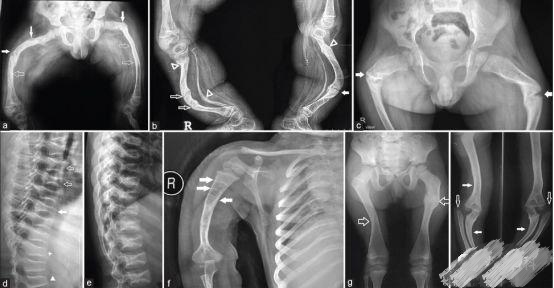

OI标志性特征是骨质脆弱反复骨折, 典型骨骼X线表现(见图二);成骨不全症的临床表现不仅限于骨骼,还常常累及其他结缔组织如眼、耳、皮肤、牙齿等(见图三)。根据临床表型, 澳洲悉尼大学的Sillence教授将OI 分成至Ⅰ-Ⅳ型[7]: Ⅰ型病情最轻, 最常见; Ⅱ最重, 通常围产期致死; Ⅲ型是存活者中最严重的, 常常身材矮小, 呈进行性骨骼畸形; Ⅳ型严重度介于Ⅰ型与Ⅲ型之间。近期发现的Ⅴ型OI 具有肥厚性骨痂、桡骨头脱位、前臂骨间膜钙化、桡骨干骺端下密集骺线等独特临床表现(见图四)。

图二:成骨不全症典型的X线表现

a.股骨干侧位片显示双侧非对称的股骨前弓弯曲愈合中的骨折(实心箭头)和已经愈合的骨折(空心箭头)

b. 胫骨侧位片显示双侧胫骨向前弯曲以及骨折愈合的不同阶段:早期愈合(实心箭头),进行性愈合中(空心箭头),已经愈合(三角);双侧胫骨呈现铅笔样畸形,尤其是腓骨及蜂巢状髓腔,特别是胫骨远端。

c. 骨盆平片显示严重的股骨近端髋内翻畸形以及基本完全愈合的转子下骨折;骨折愈合一般从内侧(压应力侧)开始,而骨折不愈合通常发生外侧表面(张应力侧);

d. 胸腰段脊柱侧位片显示椎体及附件广泛骨质疏松,椎体呈双凹征(空心箭头),扁平椎(实心箭头)以及各种程度的椎体前方楔形变,总的来说成骨不全患者脊柱骨骼改变与生长激素替代治疗的骨骼改变表现非常类似,骨硬化与骨吸收相互交错;

e. 肱骨的前后位片可以看到多条横形的硬化带,代表的是双磷酸盐治疗周期;同时还可以看到向外拉长、变薄变细的锁骨和肋骨以及增宽的肋间隙;

g.皮肤松弛症的X线片表现有时与成骨不全的比较类似,股骨干前后位片显示已经愈合的股骨干骨折;

h.上肢的前后位片显示双侧的尺骨向外侧弯曲成角,肱骨远端向内侧成角(实心箭头),同时伴有桡骨小头脱位(空心箭头)。